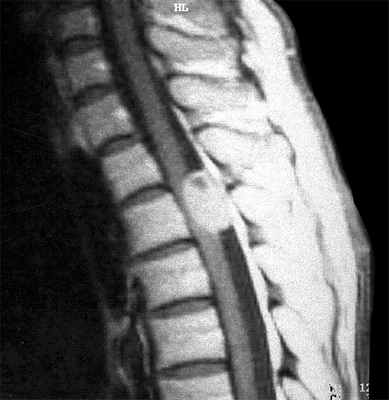

Невриномы (шванномы) и нейрофибромы составляют примерно половину опухолей этой локализации и 35% от всех спинальных опухолей. Гистологически невриномы происходят из шванновских клеток оболочек нерва (леммоцитов), прилегающих к заднему корешку. Обычно диагностируются они в возрасте 20 – 50 лет, у мужчин проявляются несколько в более молодом возрасте, чем у женщин. Они почти всегда одиночные, инкапсулированные, располагаются в любом отделе, но чуть чаще в поясничном или верхнем шейном. Множественные невриномы встречаются исключительно редко при нейрофиброматозе типа II. Нейрофибромы состоят из шванновских клеток и фибробластов, некоторые окружают задний корешок. Они почти всегда множественные и связаны с нейрофиброматозом типа I (болезнь Реклингхаузена). От 2 до 12% нейрофибром перерождаются злокачественно, превращаясь в нейрофибросаркомы. Несмотря на различие в гистологии характер роста опухолей одинаковый. Около 15% из них распространяются в экстрадуральное пространство через одно или несколько межпозвоночных отверстий, приобретая вид “песочных часов”. Такой тип роста особенно типичен для шейной локализации. На рентгенограммах рост по типу «песочных часов» может быть выявлен по расширению межпозвоночного ответстия и эрозии корня дуги. Клинические проявления неврином и нейрофибром состоят в радикулопатическом и миелопатическом синдромах.

На МРТ Т1-взвешенного типа и невриномы, и нейрофибромы изо- или слегка гипоинтенсивны по отношению к спинному мозгу. Однако, встречаются случаи и повышенного сигнала за счет сокращения Т1 мукополисахаридами, связанными с водой. Протонная плотность при МРТ повышена, а на Т2-взвешенных МРТ они чаще неоднородные, могут быть очень яркие участки, где имеется высокое содержание воды, и сравнительно низкого сигнала, особенно в центре. Обе опухоли хорошо контрастируются при МРТ. По форме невриномы округлые, границы ровные, четкие. Нейрофибромы вытянуты вдоль корешка, что лучше видно на корональных МРТ. Размеры могут быть самыми различными.

МРТ грудного отдела позвоночника. Невринома с интра-экстрадуральным типом роста. Корональная Т1-взвешенная МРТ, поперечная Т 1-взвешенная МРТ с контрастированием. Увеличение зоны интереса.

МРТ поясничного отдела позвоночника. Нейрофиброматоз тип I. Множественные нейрофибромы (стрелки). Сагиттальная и поперечная Т1-взвешенные МРТ с контрастированием, корональная Т2-взвешенная МРТ.